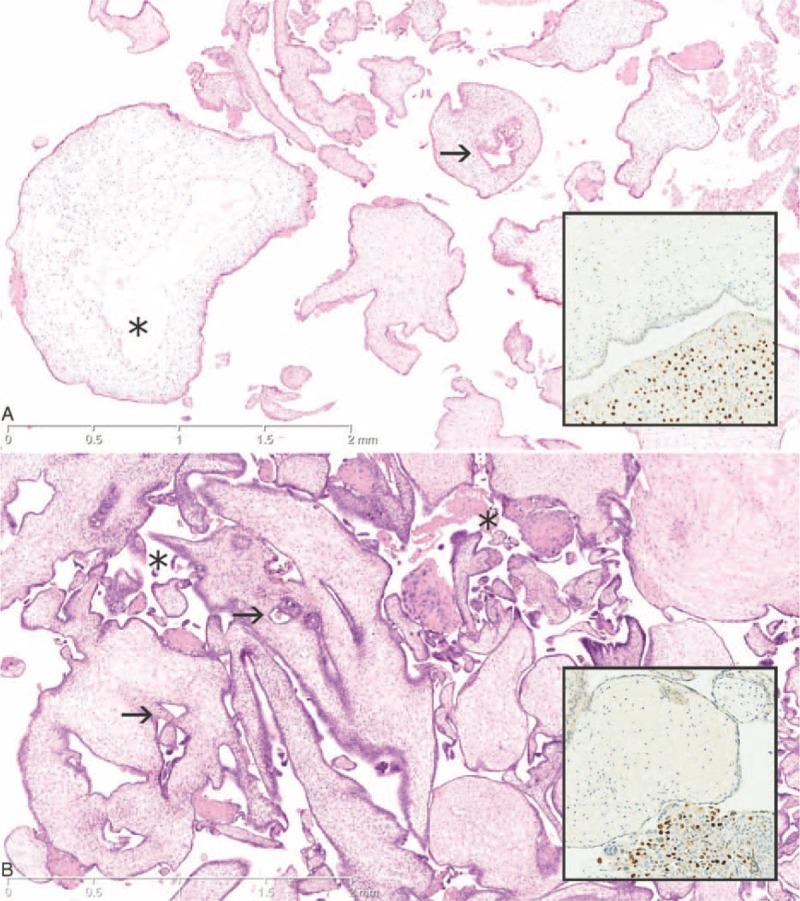

Hydatidiform mole is an abnormal human pregnancy characterized by the fetus being absent or nonviable, and the chorionic villi being vesicular and with trophoblastic hyperplasia. Most often, the mole phenotype is seen in conceptuses with an excess of paternally inherited genome set(s) relative to maternally inherited genome set(s), suggesting that the phenotype is caused by an excess of genome with a paternal imprinting pattern. However, it is unknown if correct parental origin of every imprinted gene is crucial for normal early differentiation or if abnormal parental imprinting of only one, or some, gene(s) can cause the mole phenotype.Two conceptuses included in the Danish Mole Project stood out since they presented with vesicular chorionic villi and without signs of fetal differentiation, and had apparently biparental diploid genomes, and no mutations in NLRP7 or KHDC3L were detected in the mothers. These conceptuses were subjected to a centralized histopathological revision and their genetic complements were scrutinized using fluorescence in situ hybridization, and DNA-marker and array comparative genomic hybridization analyses. Both conceptuses showed dysmorphic chorionic villi with some similarities to hydatidiform moles; however, no definite florid trophoblast hyperplasia was observed. Both conceptuses showed paternal hemizygosity of 11pter-11p15.4, most likely in nonmosaic state.Our findings suggest that the product of one (or a few) maternally expressed gene(s) on the tip of chromosome 11 is necessary for normal early embryonic differentiation. However, since the present two cases did not exhibit all features of hydatidiform moles, it is likely that abnormal parental imprinting of genes in other regions contribute to the phenotype of a hydatidiform mole.

葡萄胎是一种异常的人类妊娠,其特征是胎儿缺失或无法存活,绒毛膜绒毛呈水泡状且伴有滋养层细胞增生。大多数情况下,葡萄胎表型见于相对于母系遗传基因组而言父系遗传基因组过多的胚胎,这表明该表型是由具有父系印记模式的基因组过多所致。然而,尚不清楚每个印记基因的正确亲本来源对于正常早期分化是否至关重要,或者仅一个或一些基因的异常亲本印记是否会导致葡萄胎表型。丹麦葡萄胎项目中的两个胚胎引人注目,因为它们呈现出绒毛膜水泡状绒毛且无胎儿分化迹象,具有明显的双亲二倍体基因组,并且在母亲中未检测到NLRP7或KHDC3L的突变。对这些胚胎进行了集中的组织病理学复查,并使用荧光原位杂交、DNA标记和阵列比较基因组杂交分析对其基因组成进行了仔细检查。两个胚胎均显示出形态异常的绒毛膜绒毛,与葡萄胎有一些相似之处;然而,未观察到明确的显著滋养层细胞增生。两个胚胎均显示11号染色体末端存在父系半合子,很可能处于非镶嵌状态。我们的研究结果表明,11号染色体末端一个(或几个)母系表达基因的产物对于正常早期胚胎分化是必需的。然而,由于目前这两个病例并未表现出葡萄胎的所有特征,其他区域基因的异常亲本印记可能也对葡萄胎的表型有影响。